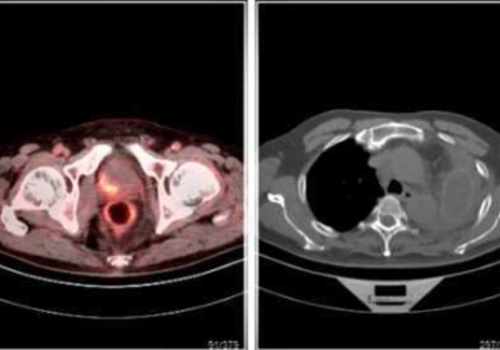

年龄:44岁检查项目:全身临床诊断:外阴錯节,CA199升高安囚显像剂(种类/剂量):18F-FDG/9.5mCi筒要病史:发现外阴结节1周,逐渐增大,伴疼痛。外院妇检:外阴:左侧大阴唇下 方扪及一约3-2cm囊块,界尚清,触痛。超声:左側大阴唇偏后侧见低回声及 无回声区,大小约19*17*19mm,形态规则,边界尚清。查,CA199 1193. 81 U/ ml: CEA、AFP, CA125,鱗状细胞相关抗原均阴性。间断性胃痛数年。甲亢3 月,治疗中。无进食;有手术史,剖宫产;无结核史;无外伤史;无糖尿病史;无肝炎 史;无传染病史;无其他疾病史;无吸烟史;无饮酒史;无家族史;月经史: 2020-7-29;意识:清楚;空腹血糖:6.0 mmol/L;检查结果: